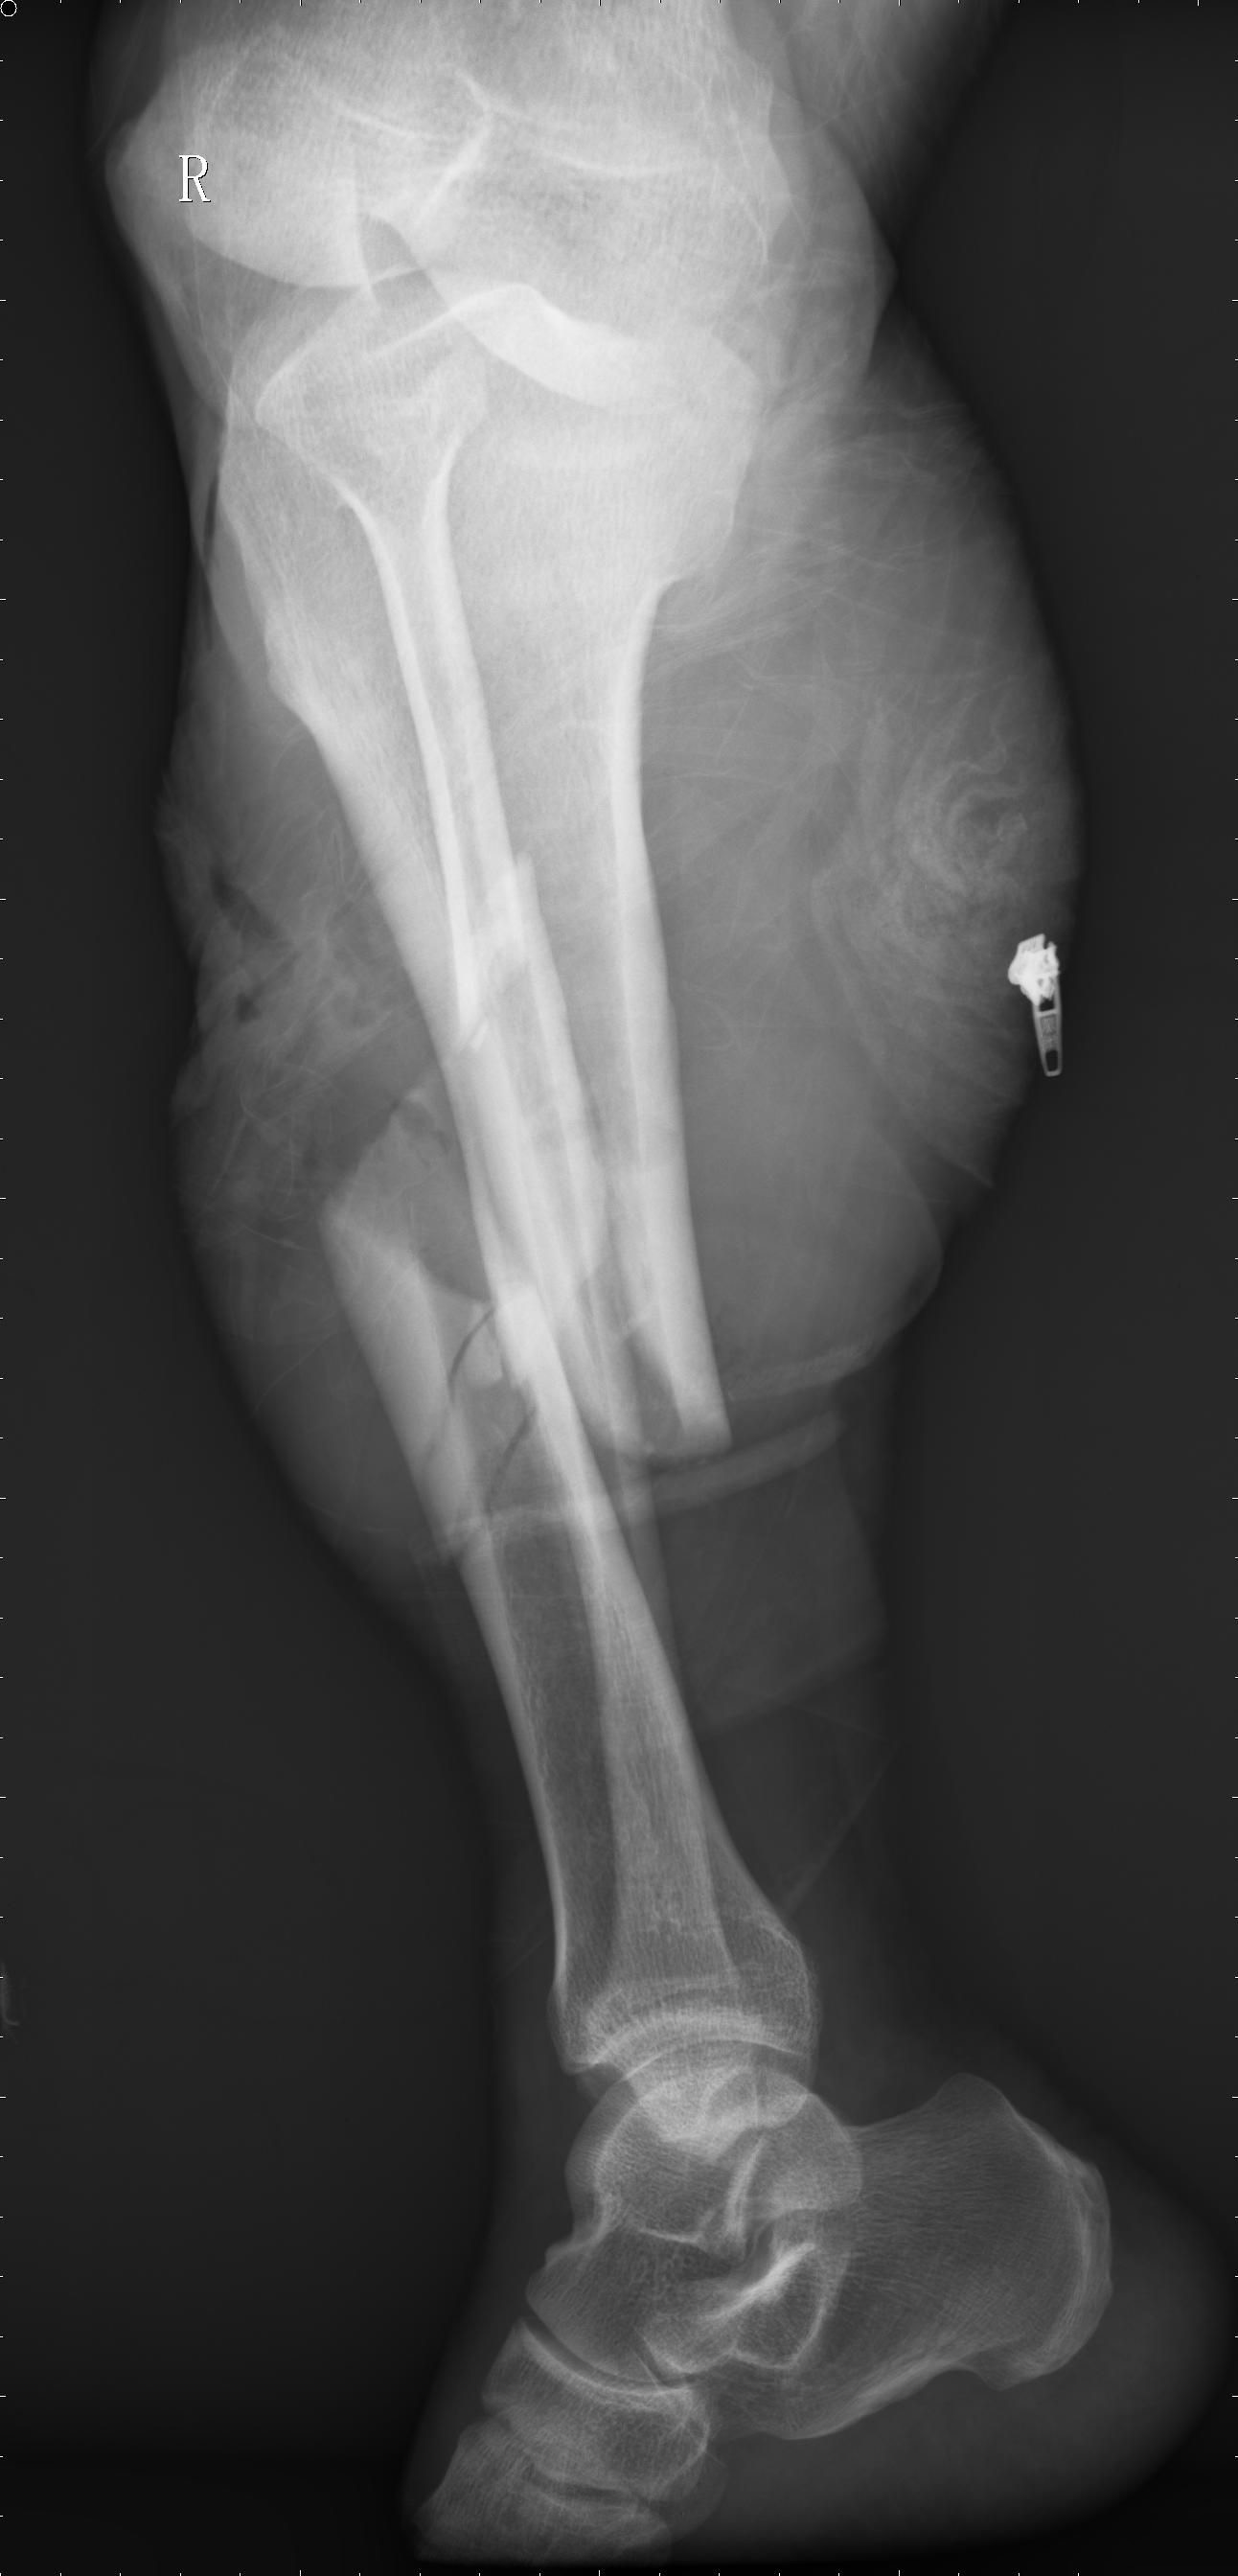

開(kāi)放性骨折的定義及應(yīng)急處理

凡骨折時(shí),合并有覆蓋骨折部位的皮膚及皮下軟組織損傷破裂,使骨折斷端和外界相通者,稱(chēng)為開(kāi)放性骨折。開(kāi)放性骨折是創(chuàng)傷骨科的常見(jiàn)病、多發(fā)病,隨著社會(huì)的發(fā)展,現(xiàn)代化高速工具的使用,所造成的開(kāi)放性骨折日趨嚴(yán)重,病情越發(fā)復(fù)雜、治療更加困難。

骨折清創(chuàng)

骨折固定是治療開(kāi)放性骨折的中心環(huán)節(jié)。骨折固定除具有維持骨折復(fù)位,保障骨折愈合,實(shí)現(xiàn)肢體早期鍛煉,促進(jìn)功能恢復(fù)的一般目的外,對(duì)開(kāi)放性骨折來(lái)說(shuō)更具有消除骨折端對(duì)皮膚的威脅,減少污染擴(kuò)散,便于重要軟組織(血管、神經(jīng)、肌腱)修復(fù),利于傷口閉合的特殊意義。

開(kāi)放性骨折的固定,60年代以前基本上是以外固定為主,主要是石膏固定;60年代初以后開(kāi)始逐漸使用內(nèi)固定,但當(dāng)時(shí)被視為違反原則。

由于內(nèi)固定所取得的良好療效,使人們信服,到70年代內(nèi)固定治療開(kāi)放性骨折已被人們接受。但內(nèi)固定治療開(kāi)放性骨折也同時(shí)出現(xiàn)不少難以解決的問(wèn)題。

70年代中期以后金屬架外固定器治療開(kāi)放性骨折如雨后春荀迅速發(fā)展起來(lái),它大大地充實(shí)了治療開(kāi)放性骨折的手段,明顯地提高了開(kāi)放性骨折的治愈率。

治療開(kāi)放性骨折不同于閉合性骨折,它容易發(fā)生感染和壞死。因此處理開(kāi)放性骨折要求迅速,盡量減少對(duì)組織的再損傷。骨折的固定方法應(yīng)以簡(jiǎn)單,迅速,有效為原則。

石膏、夾板、骨牽引雖然簡(jiǎn)單、迅速,但不能達(dá)到骨折的有效固定,骨折端的異常活動(dòng)不僅威脅傷口皮膚的愈合,更能增加污染擴(kuò)散的機(jī)會(huì);內(nèi)固定方法由于操作復(fù)雜,對(duì)嚴(yán)重污染創(chuàng)傷者感染的發(fā)生率也將因內(nèi)固定手術(shù)而大大增加。

外固定器操作迅速簡(jiǎn)便、固定可靠,調(diào)節(jié)容易且便于局部創(chuàng)面的處理,故在處理開(kāi)放性骨折中具有獨(dú)特的優(yōu)越性。

骨折固定方法的選擇,應(yīng)根據(jù)患者" 全身情況,傷口能否安全閉合及骨折類(lèi)型來(lái)判斷:Ⅰ型骨折可考慮Ⅰ期閉合傷口和骨折內(nèi)固定;Ⅱ型和Ⅲ型骨折應(yīng)優(yōu)先選用外固定器行骨外固定,后者具有方法簡(jiǎn)便,創(chuàng)傷小,并兼有骨折固定和便于觀察處理傷口的優(yōu)點(diǎn)。